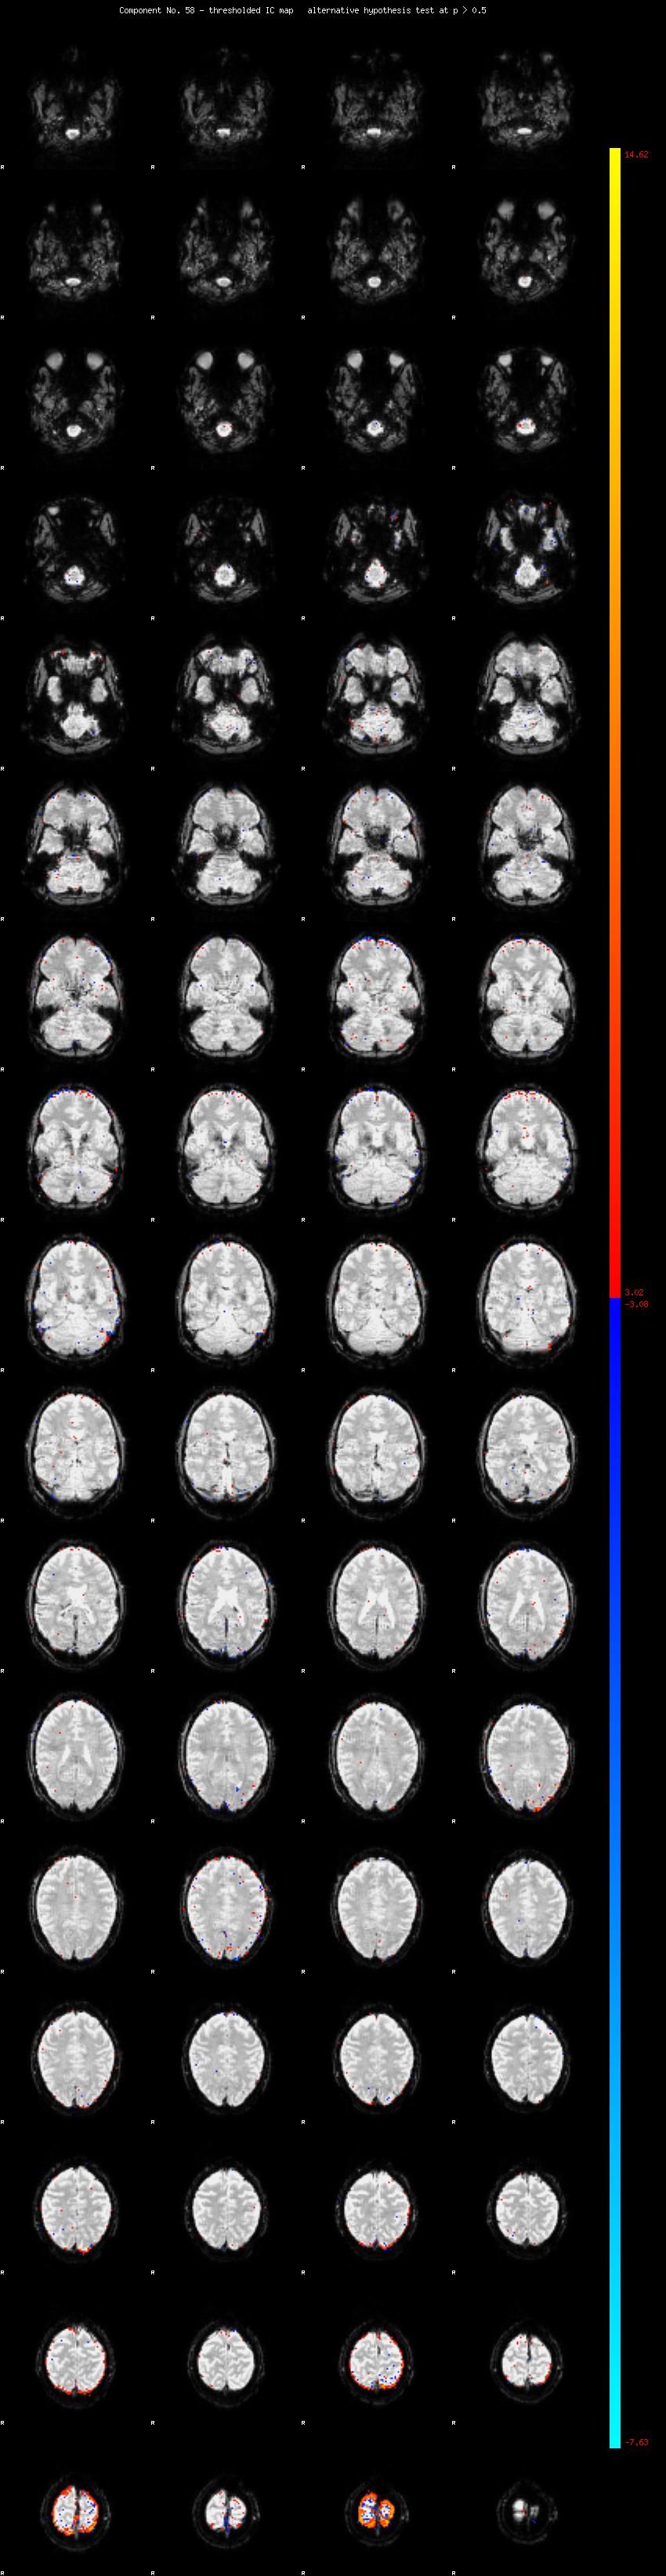

MELODIC Component 58

0.88 % of explained variance;     0.58 % of total variance

MMfit